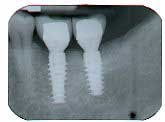

Ten months after the GBR procedure was done, a new panoramic radiograph (Fig. 4) was taken and the site was reentered for implant placement into an ideal restorative position. Dental implants (nobel active 5.0 x 11.5 mm) were placed at the No. 18 and No. 19 positions (Fig. 5), into excellent type I dense bone; note that the majority of the dental implants are completely housed in newly grafted bone. Additional minor bone grafting was done using autogenous coagulum collected during the osteotomies and a xenograft particulate (Bio-Oss, Geistlich), then covered with a resorbable collagen membrane (Biogide, Geistlich) in order to maintain buccal bone stability and contour (Fig. 6). The implants were later uncovered, ensuring that an adequate zone of keratinized tissue was present and the implants were subsequently restored (Figs. 7, 8). The success of this case was dependent upon proper treatment planning, meticulous surgical techniques, patient compliance, and understanding bone and soft-tissue biology.

Fig. 4

Fig. 5